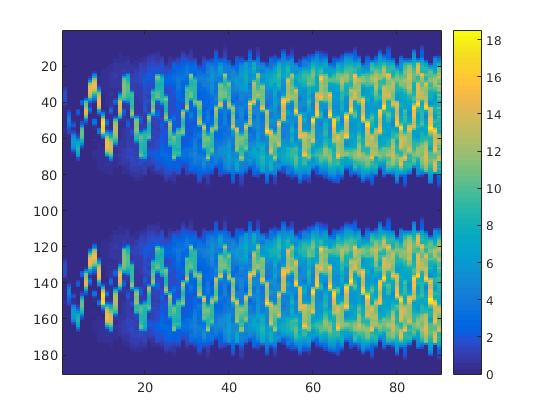

To simulate the synthesized SPECT data, we apply a Radon transform assuming a double detector gamma camera, which counts photons from two opposing projection angles per time step. For the more simple data set, we let the camera rotate clockwise around two degree per time step, in case of the complex data set we used modified projection angles, i.e. the camera alternatingly projects from an angle of i and 45+i degrees, in order to simplify the reconstruction. Each collimator consists of detector bins, so we obtain data points per time step and projection angle. The resulting sinogram data of the two underlying data sets are shown in figure 3.

In a first test, every image sequence was reconstructed out of the exact given sinograms. Additionally we tested noise corrupted data by first scaling the sinogram by a parameter , corrupting them with Poisson noise via the MATLAB imaging toolbox command imnoise and finally rescaling the image to the original range (see figure 4). The average count number per time step (i.e. the average of the discrete -norm of the data at each time step) is approximately in case of the heart-shaped data set and ca. in case of the rat liver simulation. The results at a certain number of time steps can be seen in figure 6 and 7. For comparison, we additionally performed a reconstruction with a simple alternating EM method, keeping the assumption that the tracer can be modelled as a sum of indicator functions and subconcentration curves, but neglecting any regularization terms. In all tests, the outer iteration number was set to 1000 with 10000 inner iterations per subproblem, to obtain a result within a reasonable time period. As stopping criterion, we chose the primal dual residual (cp. [12]) for the inner and the maximum over the Frobenius norms of and for the outer iterations. The results are displayed in 6 and 7 respectively.

As one can see in both figures, the reconstruction method applied to each data set performs very well, especially in contrast to the simple alternating EM method. This clearly shows the benefits of the proposed regularization methods. In case of noise-free given data, the shape of every object, where especially the heart is of higher interest, is clearly defined. As expected, we often observe errors in the edges of each region and where two regions are directly connected (the heart and the upper left circle). This causes the algorithm to incorrectly assign these pixels to another region. Furthermore, the reconstruction difficulties increase with an increase in noise. Some more pixels are assigned to the wrong region, which leads to a small hole-like structure within the heart region and causes a slight blurring effect. In the second data set the method clearly outperforms several other approaches by providing very clearly defined regions and even reconstructing fine structures of the phantom. However, as mentioned before, a clear reconstruction of the rat liver required highly optimized parameter sets, which makes the whole problem quite susceptible to parameter changes.